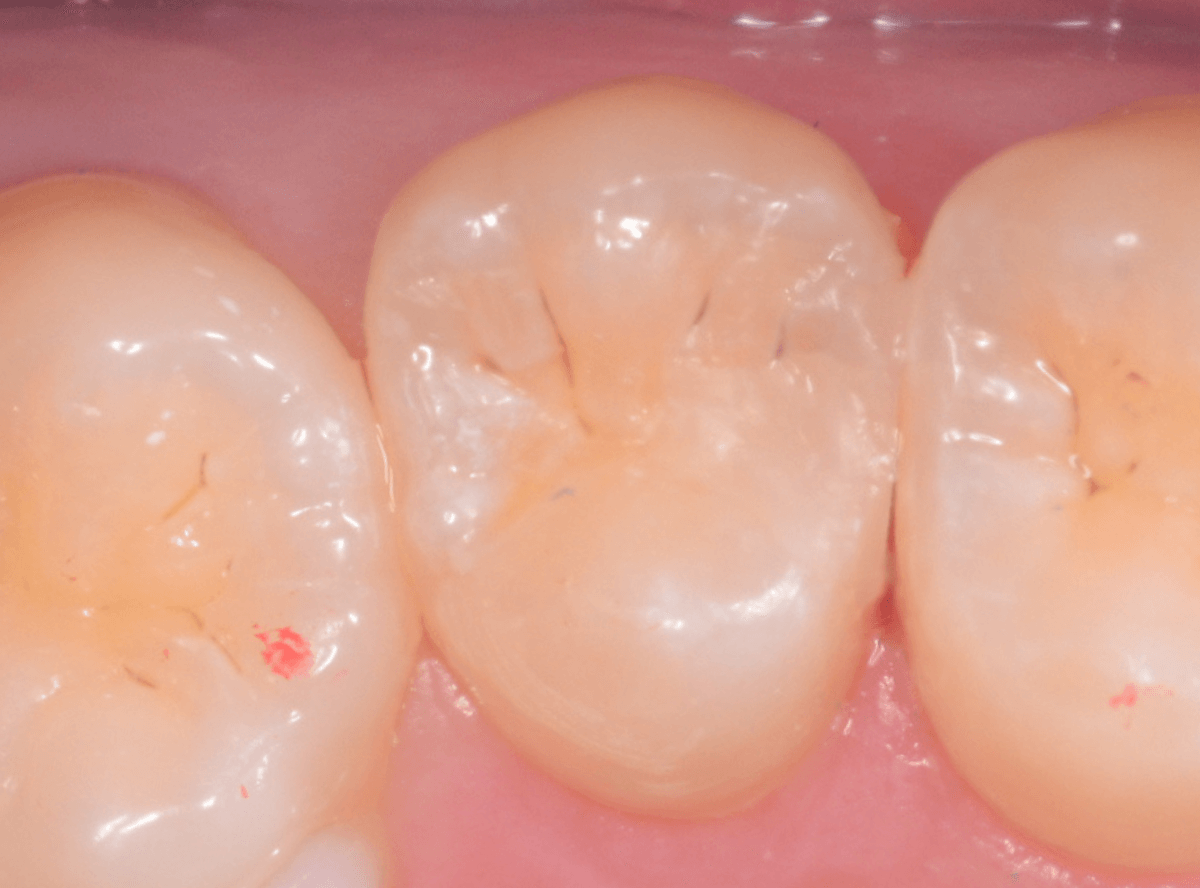

Case.7 レントゲンに写らないレジンの中の虫歯を削って調べる

こちらも定期検診希望で来院された患者さんです。

特に症状はありませんが、歯の咬頭(噛み合わせの山の部分)に小さな穴が空いていて、その周りがもやっと黒く見え、虫歯が怪しいです。

レントゲン写真で確認しますが、ここでは特に問題はなさそうに見えます。

患者さんに状況を説明し、慎重に削って調べる事になりました。

慎重に虫歯を除去したところです。

歯の溝のレジンが詰めてあった部分まで虫歯は進行していました。

とはいえ、それほど深く虫歯は進行していませんでしたので、虫歯除去後、レジンを充填して治療は終われました。

このように定期的にメンテナンスに来ていただくと虫歯が本格的に進行する前に対処する事ができます。